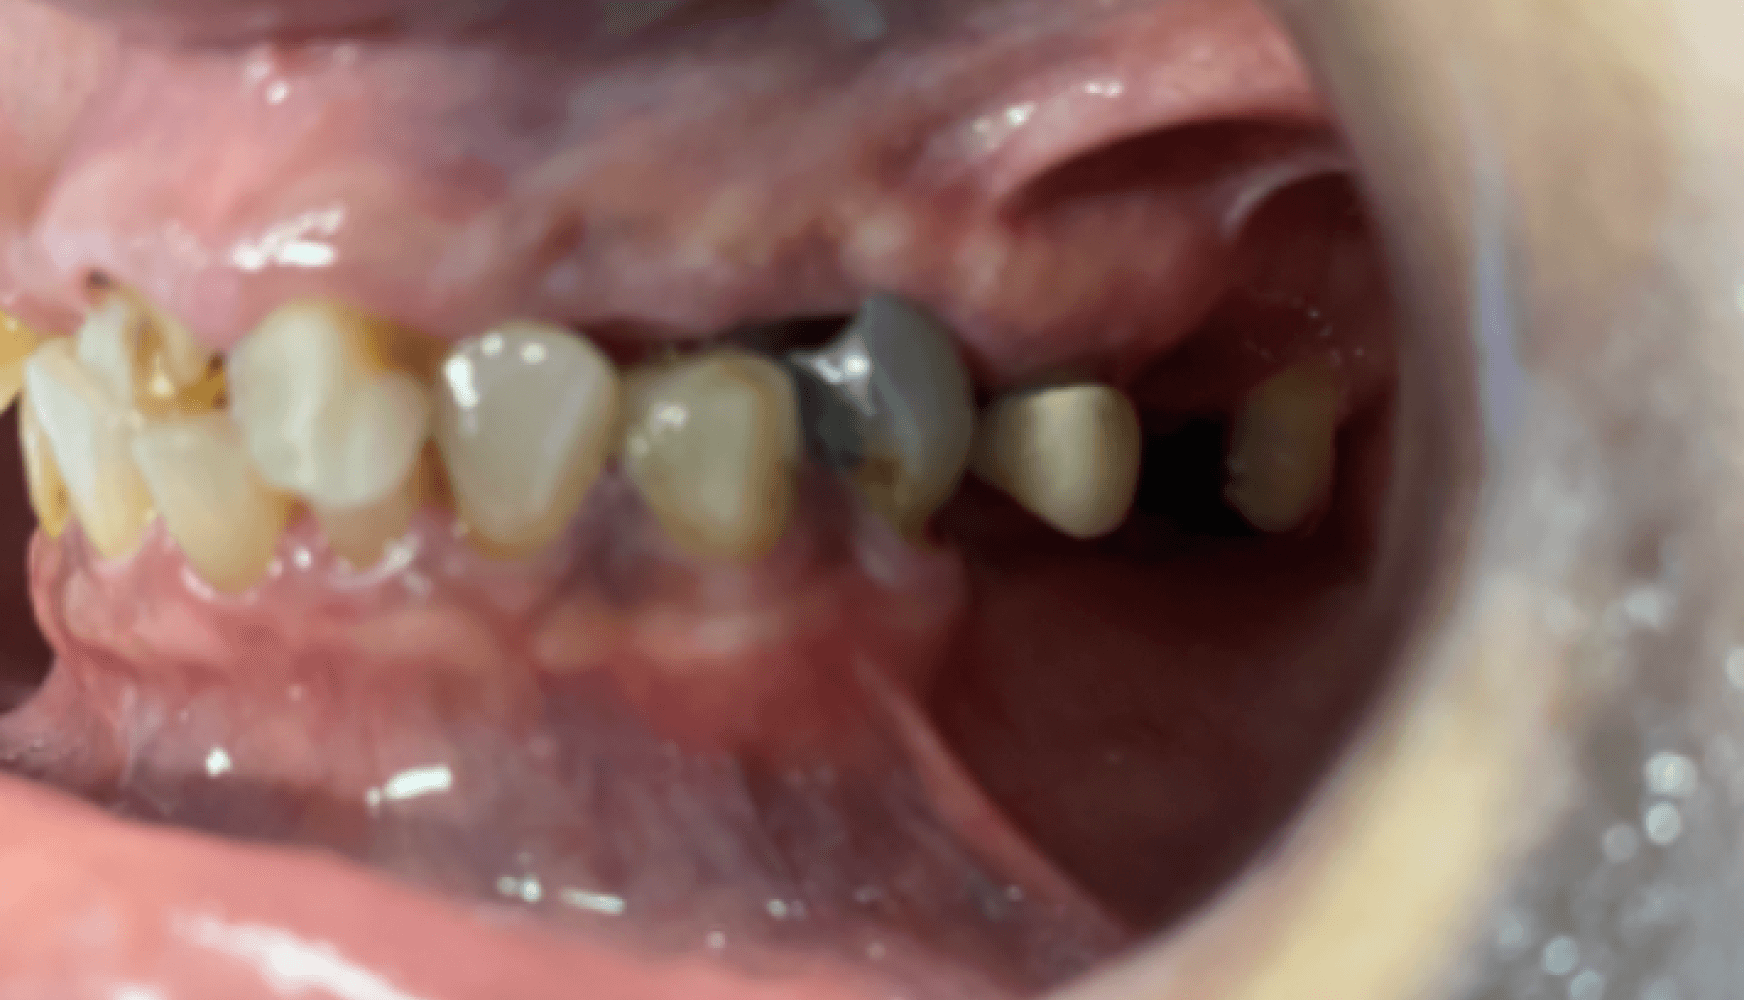

Fig. 1a, 1b, 1c, 1d: The patient’s dentition upon examination reveals significant reduction in VDO, a drastic left-to-right tilt in her smile line, and atrophy of the posterior mandibular ridge.

The patient presented with terminal dentition, multiple compromised and missing teeth, and a significant reduction in vertical dimension of occlusion (VDO) due to years of attrition and bruxism. The patient exhibited a drastic left-to-right tilt in her smile line, with significant atrophy of the posterior mandibular ridge. The right temporomandibular joint (TMJ) displayed a non-reducing disc and deviation to the right upon translation. These anatomical challenges, combined with the patient’s desire for improved function and aesthetics, necessitated a multi-phase treatment plan, beginning with immediate dentures and progressing to implant-supported dentures.